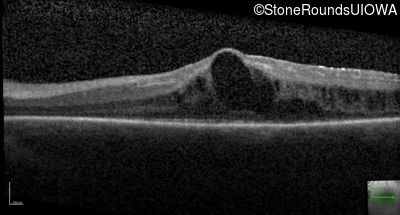

Optical Coherence Tomography - Right - 20/30 -2

Exemplar / OCT Stack